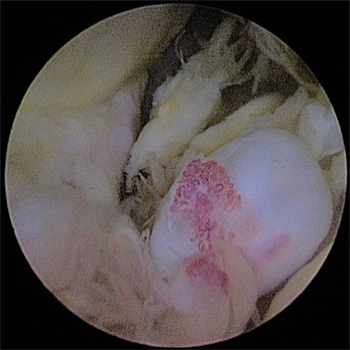

관절내시경을 통해 자라난 뼈 조각과 관절 내 유리체를 제거하며

자라난 골극을 제거해준 모습